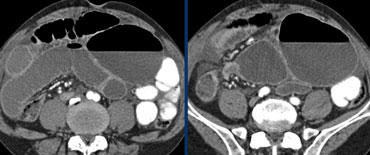

Bên trái là các hình ảnh CT bổ sung của cùng bệnh nhân nêu trên.

Đầu tiên, chúng ta thấy đại tràng xuống xẹp và đại tràng lên không giãn, do đó đây không thể là xoắn đại tràng sigma.

Thứ hai, chúng ta thấy một cấu trúc hình mỏ chim ở góc phần tư dưới bên phải, đây là vị trí xoắn của ruột.

Ở góc phần tư dưới bên trái, chúng ta thấy manh tràng giãn.